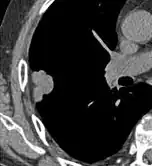

- Pleural retraction is far more common in cancers.[9] It is the pulling of visceral pleura towards the nodule.[9]

-

Nodule with pleural retraction.[9] -

In this case, pleural retraction is seen as a triangular fat component.[9]

- A lung nodule abutting a pulmonary cyst is a rare finding, yet indicating cancer.[9]